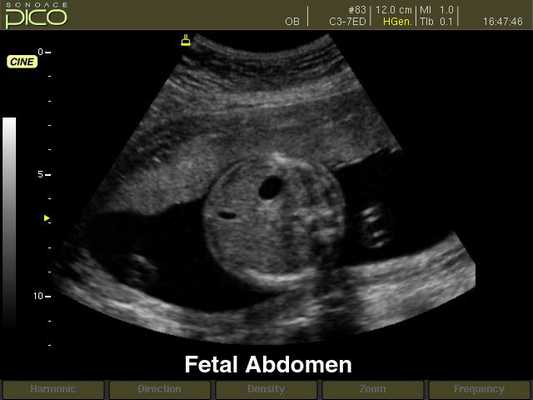

Брюшная полость плода, B-режим

[EN] Эхограмма №255: Брюшная полость плода в B-режиме.

Изображение получено с помощью УЗ аппарата SonoAce-Pico (снят с производства).